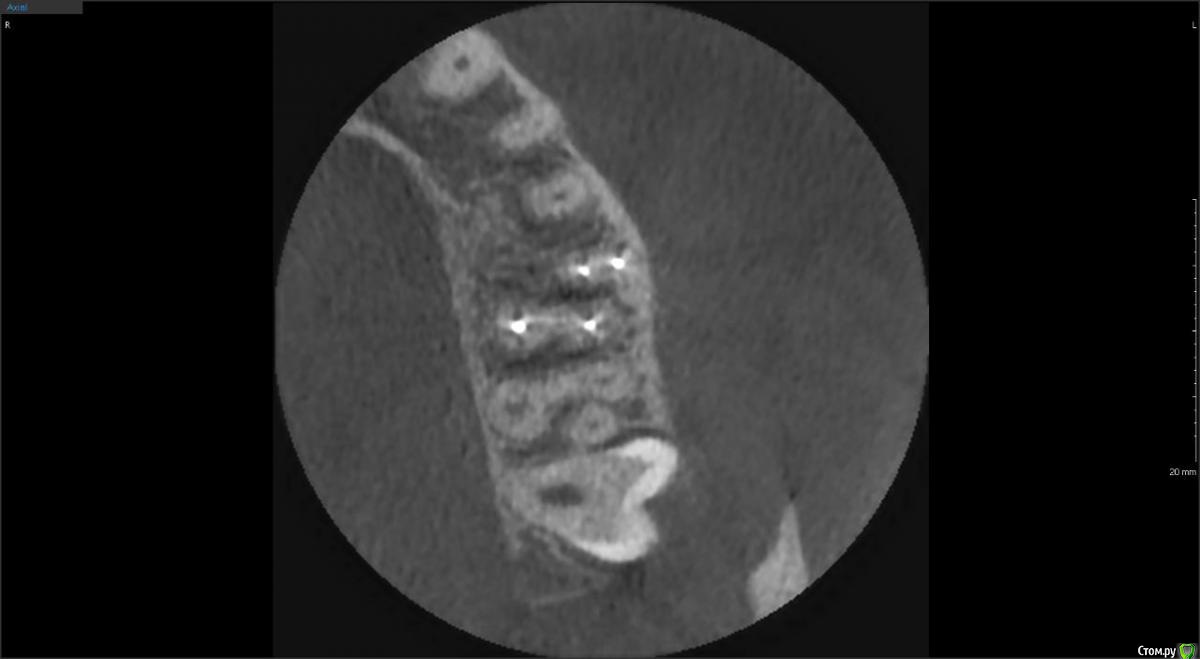

red_butler Опубликовано 4 февраля, 2020 Поделиться Опубликовано 4 февраля, 2020 Покажите ещё срезы Кт Ссылка на комментарий

Liza544 Опубликовано 4 февраля, 2020 Автор Поделиться Опубликовано 4 февраля, 2020 Вот еще пару снимков которые у меня есть. ПРошу заметить, что последние 4 снимка (файлы 7-10), которые я тут прикрепила - до пломбы на 25-м зубе и до залеченного 4-го канала в 26-м зубе. Подскажите пожалуйста, может ли быть зуб недостаточно залечен, хотя на КТ ничего подозрительного не видно? Ссылка на комментарий

ЛанаМ Опубликовано 4 февраля, 2020 Поделиться Опубликовано 4 февраля, 2020 Воспаление десны может давать постоянные ноющие боли и боль при накусывании. От чистки сразу не пройдет, нужно дней 5-7 противоспалительного лечения и отсутствие травмирования (постараться ниткой не чистить). Также нужно убедиться, что нет хронического воспаления в гайморовой пазухе. Побольше срезов кт, желательно уже после пломбирования четвертого канала. Да, бывают проблемы в зубе и при идеальной картинке рентгеновского снимка. На нем видны только крупные каналы, а там еще целая сеть мелких. Ссылка на комментарий